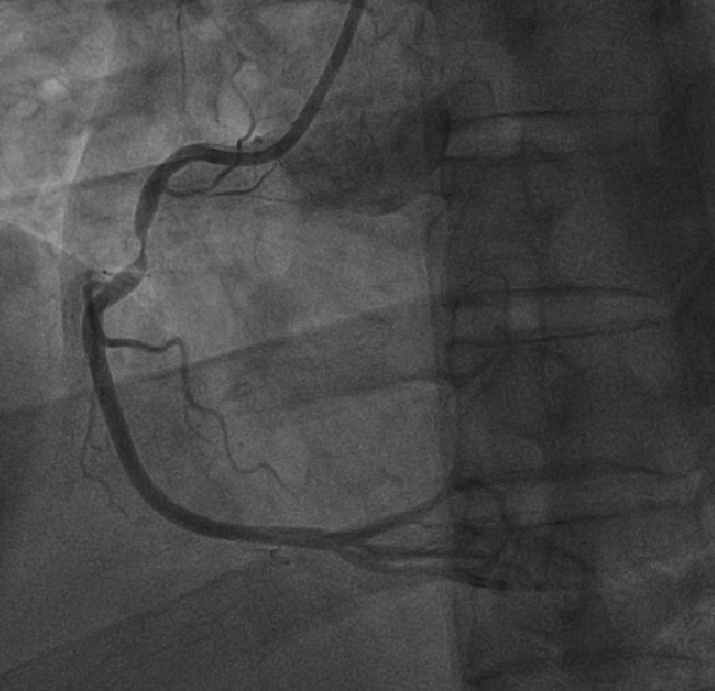

患者到达导管室后,张丙坤主任带领的介入团队立即为患者实施紧急介入治疗,并顺利开通血管,患者胸闷症状明显减轻。术后转入心血管内科二区病房继续治疗。

术后